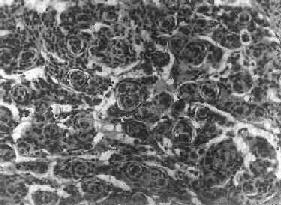

图16-23 星形胶质细胞瘤 左大脑半球肿胀,肿瘤边界不清,部分呈胶冻状 镜下,肿瘤细胞形态多样,可相似于纤维型星形胶质细胞、原浆型星形胶质细胞和肥胖星形胶质细胞,故分别称为纤维型、原浆型和肥胖型星形胶质细胞瘤。前二者为良性肿瘤,后者性质介于良恶性之间。如肿瘤细胞出现间变,细胞密度增大,异型性明显,核深染,出现核分裂像,毛细血管内皮细胞增生,则为间变性星形胶质细胞瘤,为恶性肿瘤。 高度恶性的星形胶质细胞瘤称为多形性胶质母细胞瘤(glioblastoma multiforme),多见于成人。肿瘤好发于额叶、颞叶白质,浸润范围广,常可穿过胼胝体到对侧,呈蝴蝶状生长(图16-24)。瘤体因常有出血坏死而呈红褐色。镜下,细胞密集,异型性明显,可见怪异的单核或多核瘤巨细胞。出血坏死明显,是其区别于间变性星形胶质细胞瘤的特征。毛细血管明显增生,内皮细胞增生、肿大,可导致管腔闭塞和血栓形成。肿瘤发展迅速,预后极差,患者多在2年内死亡。

图16-24 多形性胶质母细胞瘤 发生于儿童、青少年的毛发细胞型星形胶质细胞瘤,生长极为缓慢。有报道称患者在不完全切除肿瘤后有带瘤存活达40年者。该瘤常位于小脑、第四脑室底部、第三脑室、丘脑和视神经。其形态特点是由双极性的肿瘤细胞两端发出纤细的毛发状突起。即使有毛细血管增生,本瘤的预后仍相对较好。 应该指出,同一肿瘤的不同区域,瘤细胞可有不同的形态特征,且分化程度也不尽相同,因此肿瘤的分型仅具有相对的意义。 星形胶质细胞瘤的细胞骨架含有胶质纤维酸性蛋白(GFAP),免疫组织化学染色呈阳性反应,是该肿瘤的特异标志。 2.少突胶质细胞瘤(oligodendroglioma) 约占颅内胶质瘤的5%,主要见于30~40岁的成人,男女发病的机会相等。本瘤绝大部分位于大脑半球皮质的浅层,尤以左额叶为多见。 肉眼观,肿瘤呈灰红色边界清楚的球形肿块,位于白质和邻近的皮质,并可累及软脑膜。囊性变、出血和钙化颇为常见,其中钙化灶对X线诊断有一定帮助。 镜下,瘤细胞大小均匀,形态单一,弥漫排列,胞核居中着色深,胞浆空,环绕胞核形成空晕。间质富有血管,有不同程度的内皮细胞增生。约有20%病例可出现瘤细胞钙化,其范围大小不一,其中7%为镜下钙化,有时钙化灶较大,可在X线片上显示出来。如肿瘤组织中混有星形胶质细胞瘤成分达到50%,则称混合性少突星形胶质细胞瘤。 本瘤生长缓慢,病程可长达10~30年,临床表现多为癫痫和局部性瘫痪。少数生长迅速,酷似多形性胶质母细胞瘤,预后不佳。 3.室管膜(细胞)瘤(ependymoma)起源于室管膜细胞,患者多为儿童和青少年。本瘤占颅内胶质瘤的5%~6%,多见于第四脑室,其次为侧脑室、第三脑室和导水管。脊髓病变多发生于腰胝及马尾部。 肉眼观,颅内室管膜瘤呈膨胀性生长,边界清楚,呈球形、分叶状或乳头状,肿瘤多在脑室内生长。切面灰白色,呈均匀或颗粒状,可发生灶性出血甚至坏死或囊性变,有时也可发现点状钙化。 镜下,瘤细胞大小形态一致,呈梭形或胡萝卜形,胞核圆或椭圆,染色质呈细颗粒状,核膜清楚,有核仁。瘤细胞胞浆丰富,突起明显。瘤细胞的排列有二种特征,一是环绕空腔排列成腺管状,形态上与室管膜腔相似,称为菊形团形成,另一是环绕血管形成假菊形团结构,瘤细胞有细长的胞浆突起与血管壁相连(图16-25)。细胞中有神经胶质纤维,以PTAH染色在个别细胞的腔面或胞核旁可见纤毛体,后者与纤毛运动有关,是室管膜细胞的特征性结构。此外,有时还可形成乳头状结构。发生在脊髓圆锥和终丝的肿瘤,乳头状结构轴心中的结缔组织往往富含粘液。